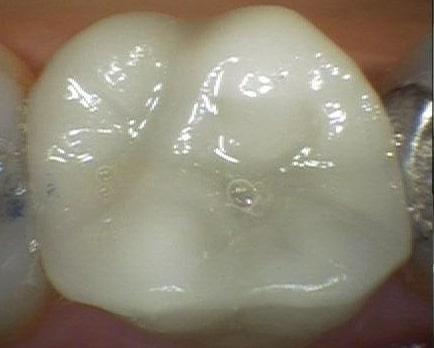

Ceramic Crown

This patient had an old and failing metal filling, and there were visible cracks on her back molar. She wanted to restore the tooth with something that looked natural, so a ceramic crown was chosen. These types of restorations are both strong and beautiful.